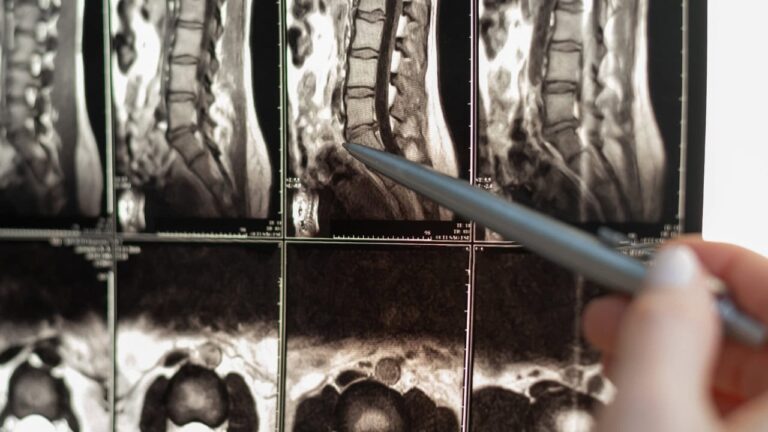

In some cases, entrapment neuropathies arise in the spine, such as in cervical or lumbar radiculopathies. These conditions occur when nerve roots become compressed, often due to herniated discs or degenerative changes in the spine. While these disorders may seem distinct, they share the underlying mechanism of nerve compression or irritation, leading to a variety of sensory and motor symptoms.

Advanced diagnostic tools, such as MRI and electrodiagnostics, are useful tools for confirming the diagnosis in complex cases. MRI is useful for identifying structural changes in tissues provoking neuropathies, while nerve conduction studies can assess the functional status of the affected nerves.ars and it commonly accompanies them throughout their productive years. This timing poses a significant challenge, as migraines are predominantly experienced when individuals are often focused on careers, work, and raising children. After reaching this peak, many people experience a gradual decline in the frequency of migraines as they age, especially women, who may notice a reduction in migraine occurrences around menopause.

The future of entrapment neuropathy diagnosis and treatment is promising, thanks to advances in imaging and precision medicine. Ultra-high-field MRI and MR neurography are paving the way for more accurate diagnostics by allowing clinicians to visualize nerves in unprecedented detail. These techniques are particularly valuable for identifying subtle changes in nerve structure that may not be visible with traditional imaging.